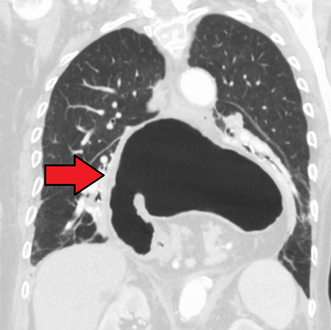

فتق حجابي كما يظهر بالتصوير المقطعي المحوسب.

-

فتق حجابي كبير كما يظهر بالتصوير المقطعي المحوسب.